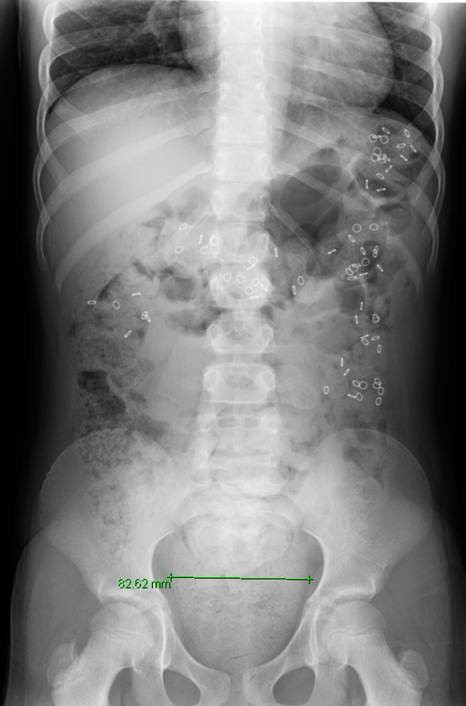

If your child has functional constipation and is not responding well to a bowel management program, pediatric colorectal specialists and gastroenterologists will perform a series of diagnostic tests to determine the underlying cause of the condition.

If your child is a candidate for surgery, the type of surgery your child will need and when to perform it is based on a comprehensive evaluation of the anorectal and colorectal anatomy and physiology.